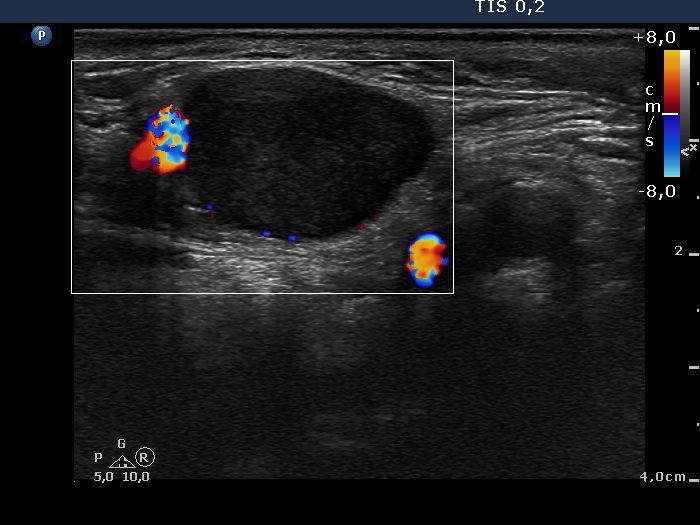

Ultrasonography. There was a hypoechogenic nodule presenting microcalcification in the ventromedial part of the right lobe. Corresponding to the palpable mass in the right submandibular area, a lymph node was found. The node did not present hilum.